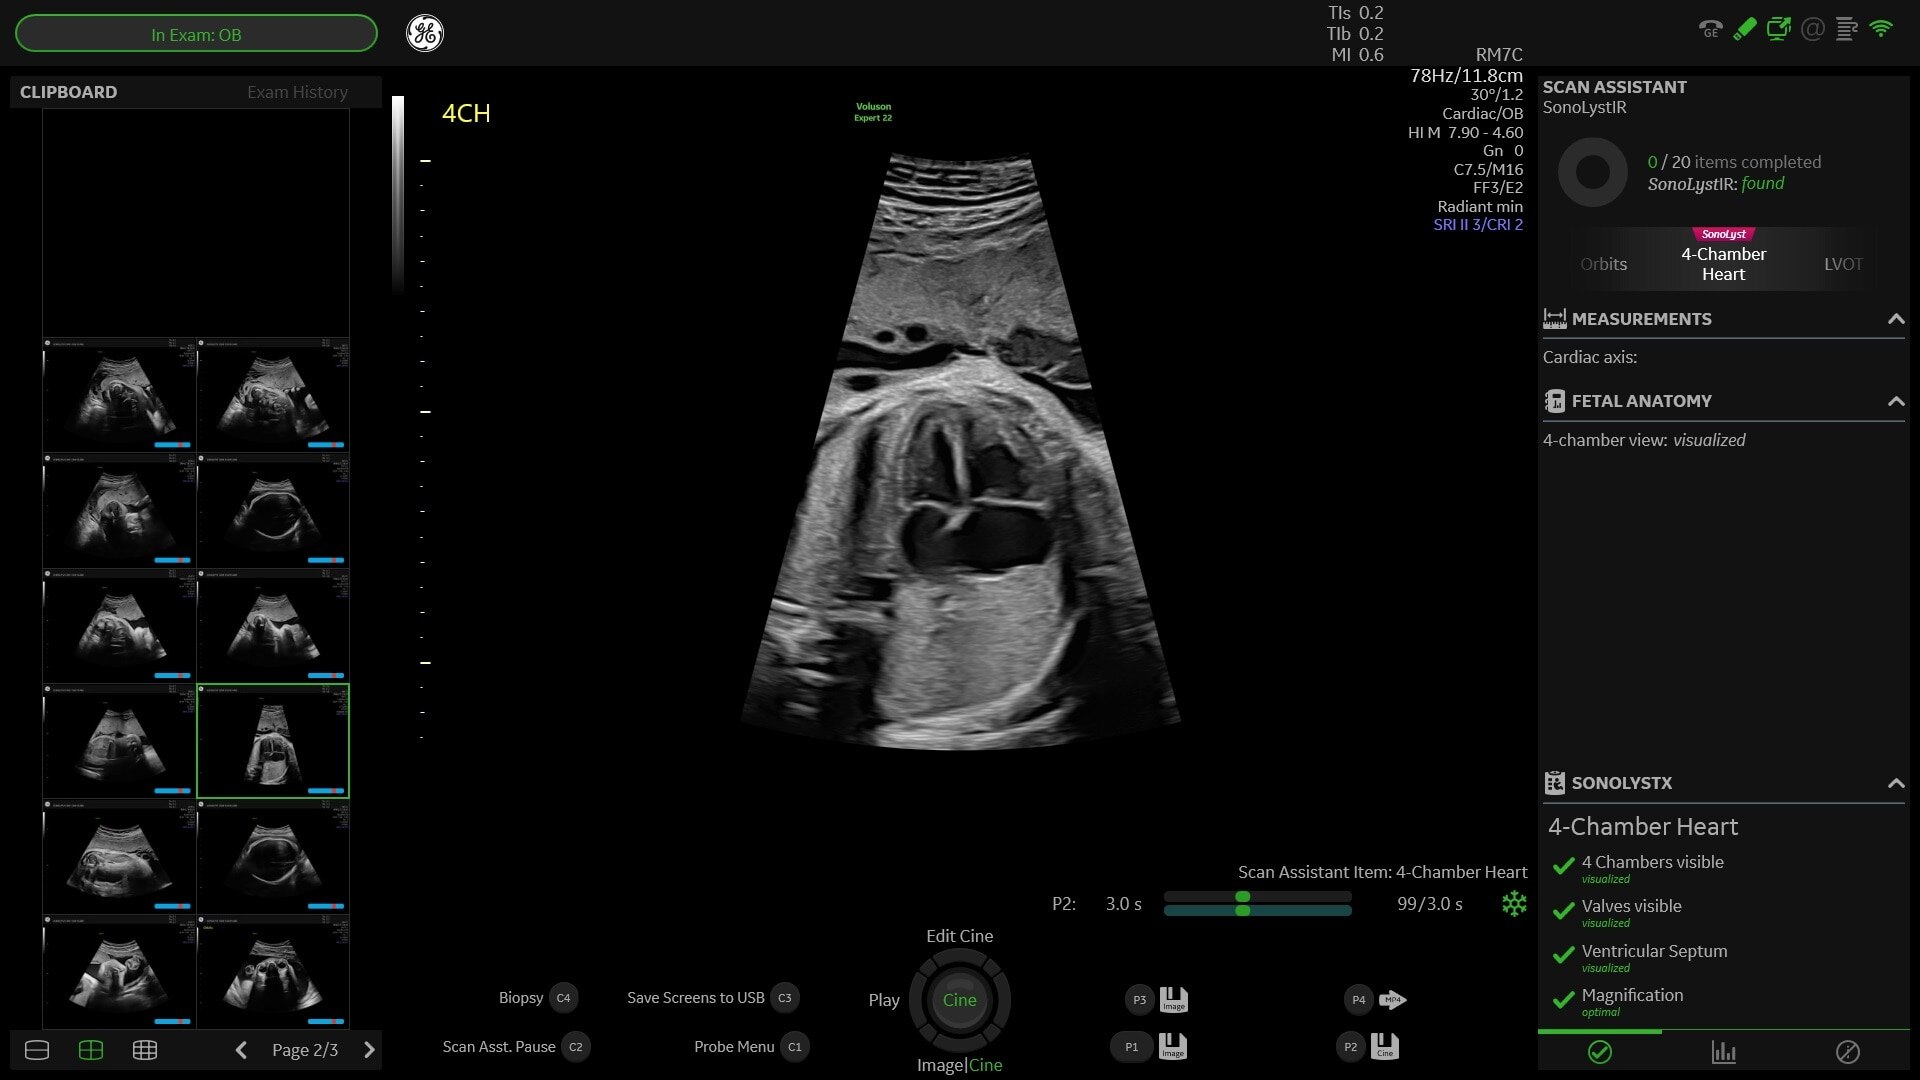

• SonoLystIR: Simply scan, then freeze and SonoLystIR (Image Recognition) does the rest.

• SonoLystX: Build and refine your skills with SonoLystX. Using AI, the system compares the image or view acquired to standard criteria accepted by experts to ensure it meets clinical standards.